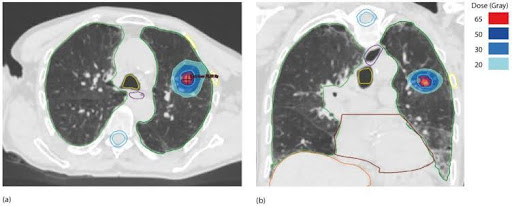

Abbildung 2: Die vorliegende Abbildung zeigt ein Beispiel für die Anwendung einer SBRT bei einem metastasierten Lungenkarzinom: Dosimetrie einer 55-Gy-Lungen-SBRT in fünf Fraktionen zu je 11 Gy bei Lungenmetastasen eines primären Lungenkarzinoms. (a) Axiale Ansicht, (b) koronale Ansicht. Das Bruttotumorvolumen (GTV) ist rot, das Planungszielvolumen (PTV) blau und die Markerpunkte sind grün dargestellt.2